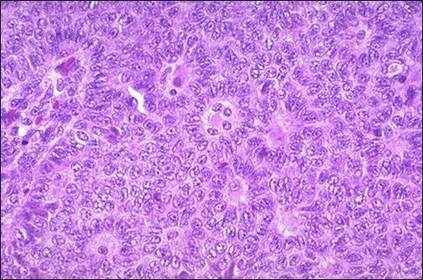

Adenocarcinoma de Endométrio Grau I.

Adenocarcinoma de Endométrio Grau II.

Adenocarcinoma de endométrio grau III.

Descreva os estágios de classificação do adenocarcinoma de endométrio. Grau I - Predomínio de Glândulas (bem diferenciado). Grau II - Glândulas em proporção semelhante à área sólida (moderadamente diferenciado). Grau III - Há predomínio de áreas sólidas (cels epiteliais proliferadas), (pouco diferenciado).